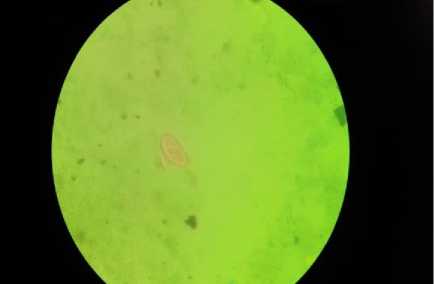

Dari pemeriksaan feses, hanya terdapat satu jenis spesies cacing usus yang menginfeksi responden yaitu Enterobius vermicularis, dimana didapatkan satu buah telur cacing Enterobius vermicularis melalui pemeriksaan laboratorium. Temuan telur cacing Enterobius vermicularis dapat dilihat pada gambar 1 Berikut.

Gambar 1 Temuan telur cacing Enterobius vermicularis pada pemeriksaan Sampel feses dengan perbesaran 10x

objektif